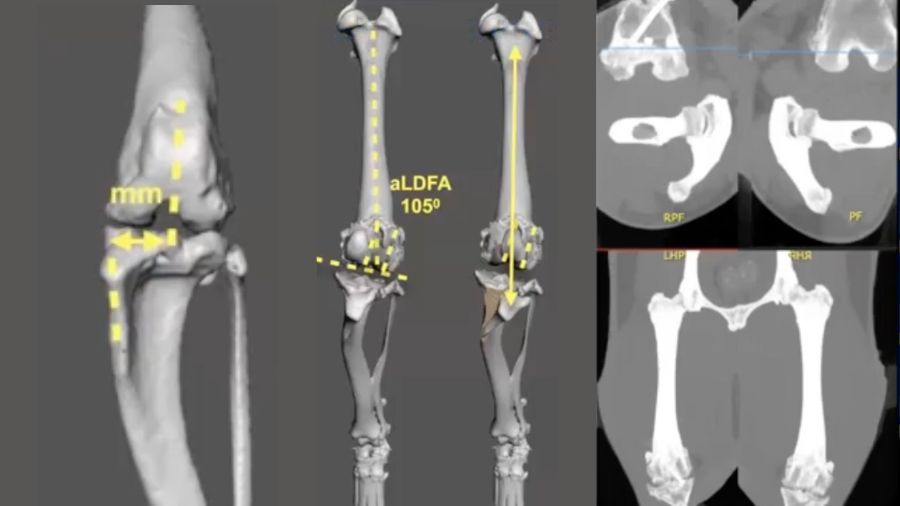

This is apparent in the CT renderings in Fig 7 (10:19) where a major translation of the tibial tuberosity has been simulated, resolving the frontal plane offset, but because of the unresolved significant femoral varus, the patella is tracking obliquely and quite abnormally through the trochlea. Even by forcing the patella to stay in place with a failed ridge replacement (Fig 8 10.54), you would still get abnormal tracking, erosion, and significant pain. An oblique trochlea creates abnormal patellar tracking and abnormal retropatellar pressures and is not a benign thing. So it is important to understand that managing more complex patella luxation cases is not just about keeping the patella from luxating.

For the femur, the amount of torsion between the head and neck of the proximal femur and the condyles of the distal femur is called the femoral anteversion angle (FAA) and ranges between 16–31°. In Fig 10 (12:53), on the right is an axial plane view of the distal femur showing the condyle, and on the left an axial plane view of the proximal femur along the angle of inclination. The methodology for this has been previously published so we won’t go into detail in this article. Again, the Atlas of Clinical Goniometry and Radiographic Measurement of the Canine Pelvic Limb by Massimo Petazzoni and Gayle H Jaeger is an excellent reference source.